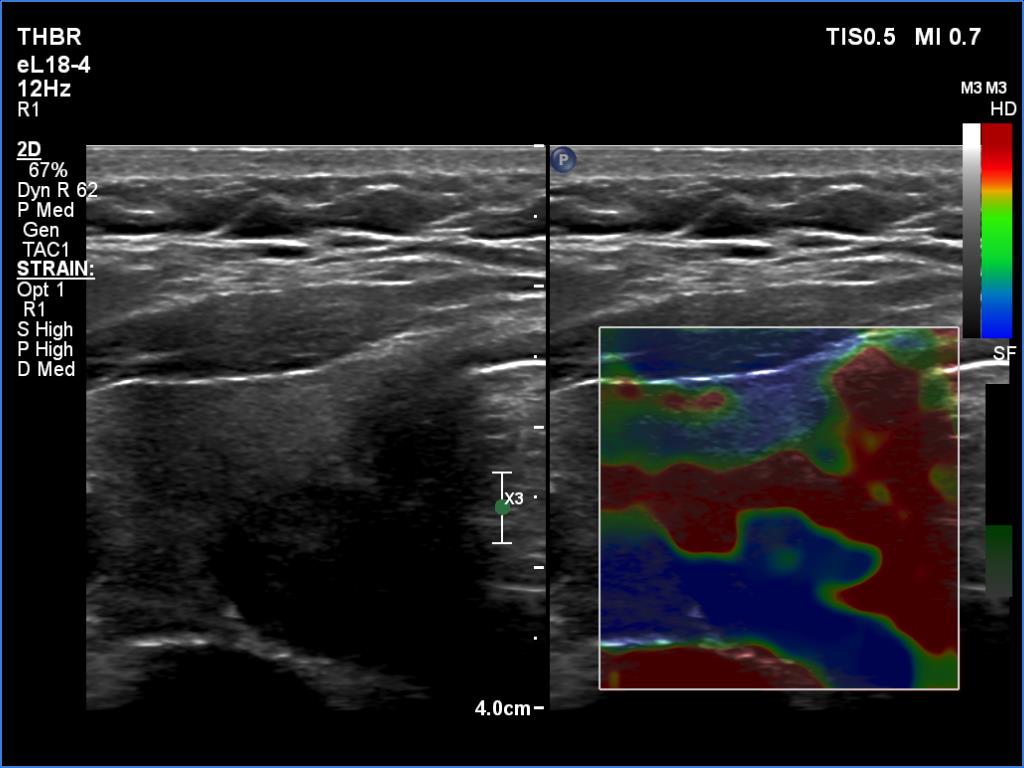

Ultrasonography. The thyroid was echonormal. The cyst has not refilled. There was a moderately hypoechoic nodule with signs of cystic degeneration in the left lobe. The nodule showed irregular, lobulated margins. I present two elastography images which demonstrate the usual finding in cytic lesions: there is a stratification of levels with different elasticity irrespectively of benign or malignant origine of cystic nodule.